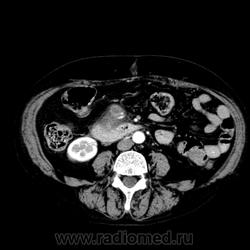

Уважаемые коллеги!Сразу предупреждаю-верификации диагноза не будет, так как пациентка из Средней Азии и после исследования собиралась уехать домой.Обратилась она на УЗИ с жалобами на боли в животе,врач УЗИ предположил наличие опухоли головки подж. ж-зы и рекомендовал РКТ..Были проведено нативное исследование и  РКТ с в/в болюсным усилением (100 мл омнипака300 со ск. 3 мл./сек) на 25 и 95 секундах после введения контрастного вещества.В головке подж. ж-зы определяется образование округлой формы 57 мм в диаметре.В его передних отделах-гиподенсное содержимое плотностью +40+42 едН,в задних отделах-содержимое плотностью +60+66 едН. На 25 секунде в передних отделах определяется интенсивно накопившее контрастное вещество образование округлой формы размерами 22х24 мм,плотностью +190 едН(плотность брюшной аорты при этом +260+270 едН),содержимое в задних отделах не накопило контрастное вещество.На 95 секунде от введения плотность гиперваскулярного образования +127 едН(аорты+115 едН).Кроме того, визуализируется капсула,окружающая указанные структуры.Холедох не расширен.Вирсунгов проток в области головки и тела расширен до 5-6 мм,в хвосте-до 3-4 мм.

Связи гиперваскулярного образования с сосудами не выявлено.Собрав конвульсиум из 4-х врачей мы предположили,что у пациентки может быть псевдокиста головки поджелудочной железы со сгустком крови в задних отделах и гиперваскулярной опухолью (возможно инсулиномой) в передних отделах.

Некое подобие частично тромбированной псевдоаневризмы. Естественно, сама по себе она не появляется. Внимательно смотреть связь с сосудами, они не обязательно должны быть крупными. И какой анамнез, о.панкреатит был? На инсулиному и цистаденокарциному не похоже IMHO. Покрутить бы серию. Автор, про гиперваскулярную массу, что указана стрелками - это однозначно не опухоль, это псевдоаневризма.

Спасибо,коллеги,похоже это псевдоаневризма в стенке постнекротической кисты.Прилагаю ссылку -http://meduniver.com/Medical/Xirurgia/342.html.

Кровь же не моментально лизируется, проходит стадии, которые по-разному видятся на КТ. Тут до полного лизиса не дошло, выглядит как подострое кровоизлияние. По плотности тоже на мягкотканный компонент опухоли и грануляции не тянет, чисто кровь, такое мое мнение. Далее, где-то через недели полторы-две она будет выглядет как жидкость, если не подкровит. Про все остальное - чисто домыслы, об этом можно думать и рассуждать, но писать эти догадки смысла особого нет...

Согласна с Сергеем Николаевичем, картина пседокисты с тромбами разного возраста. Вероятно подкравливает.